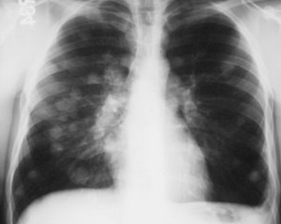

Rx toracică, incidență P-A

DESCRIERE:

pe tot teritoriul pulmonar, bilateral → opacități nodulare multiple de dimensiuni variabile, intensitate medie-mare, omogene, cu contur imprecis delim

confluente

distribuție anarhică

DX: bronhopneumonie

DD:

miliara TBC

MTS pulm hematogene